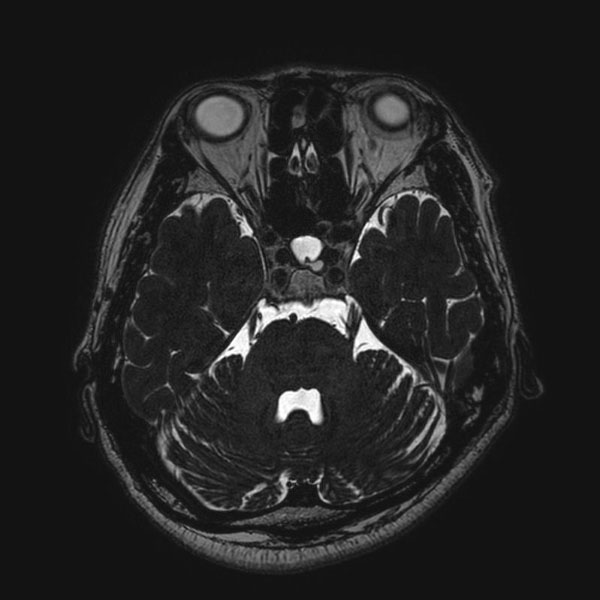

症例 '26年2月

No.

577

大阪府の病院

'26年2月

40代

右顔面痙攣

(痙攣をとること)

手術前

減圧前

減圧後

術後血管撮影